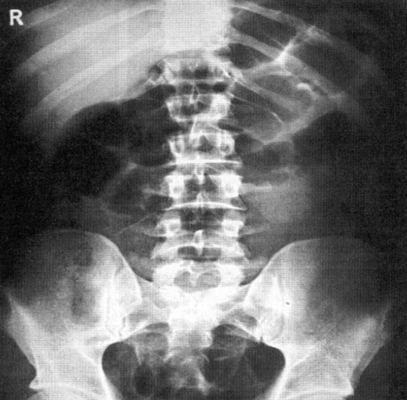

Назначение снимка—получение общего представления о положении, форме и размерах органов живота, а также выявление свободного газа в брюшной полости, уровней жидкости в раздутых газом петлях кишок (чаши Клойбера), обызвествлений и конкрементов в проекции желчного пузыря и почек, металлических инородных тел в брюшной полости или брюшной стенке. Кроме того, в отдельных случаях к обзорной рентгенографии живота прибегают в акушерской практике с целью определения числа,

Информативность снимка. На обзорной рентгенограмме (электро-рентгенограмме) живота отображаются очертания печени, почек, больших поясничных мышц, желудка и кишечника (при наличии в них газа), а также диафрагма, вход в малый таз и боковые каналы брюшной полости (рис. 538).

На правильно выполненном снимке должны быть хорошо видны очертания паренхиматозных органов живота, диафрагма, нижние ребра, проксимальные отделы подвздошных костей и боковые отделы брюшной полости.

Позвоночник при симметричной укладке и отсутствии сколиоза располагается по средней линии снимка.

Наиболее частые ошибки при выполнении снимка — неправильное положение (смещение кверху, книзу или вбок) кассеты или неправильное направление центрального пучка излучения, в результате чего на снимке отсутствует изображение диафрагмы, подвздошных костей или боковых отделов живота.

Рентгенологическая диагностика повреждений органов брюшной полости в остром периоде травмы базируется на выявлении свободного газа (пневмоперитонеум) и жидкости (гемоперитонеум), наличии нечеткости и увеличения изображения паренхиматозных органов (печень, селезенка, почки), а также инородных тел в брюшной полости.